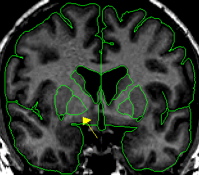

| General Description  In the coronal view the pallidum resembles a rounded triangle that continues off the putamen. The pallidum starts anteriorly as a small triangle and reaches its largest extent in its most medial slices and then dwindles to a small triangle again in the most posterior slices. The pallidum is essentially surrounded by white matter except for the lateral border which is the putamen. The putamen and pallidum are separated at this border by a thin strip of white matter called the lateral medullary lamina. Medially, pallidum is difficult to discern from the surrounding white matter because although it is gray, in terms of its intensity, its darkness is frequently fainter than putamen.  Procedure | |

The final outline should be labeled "pallidum."